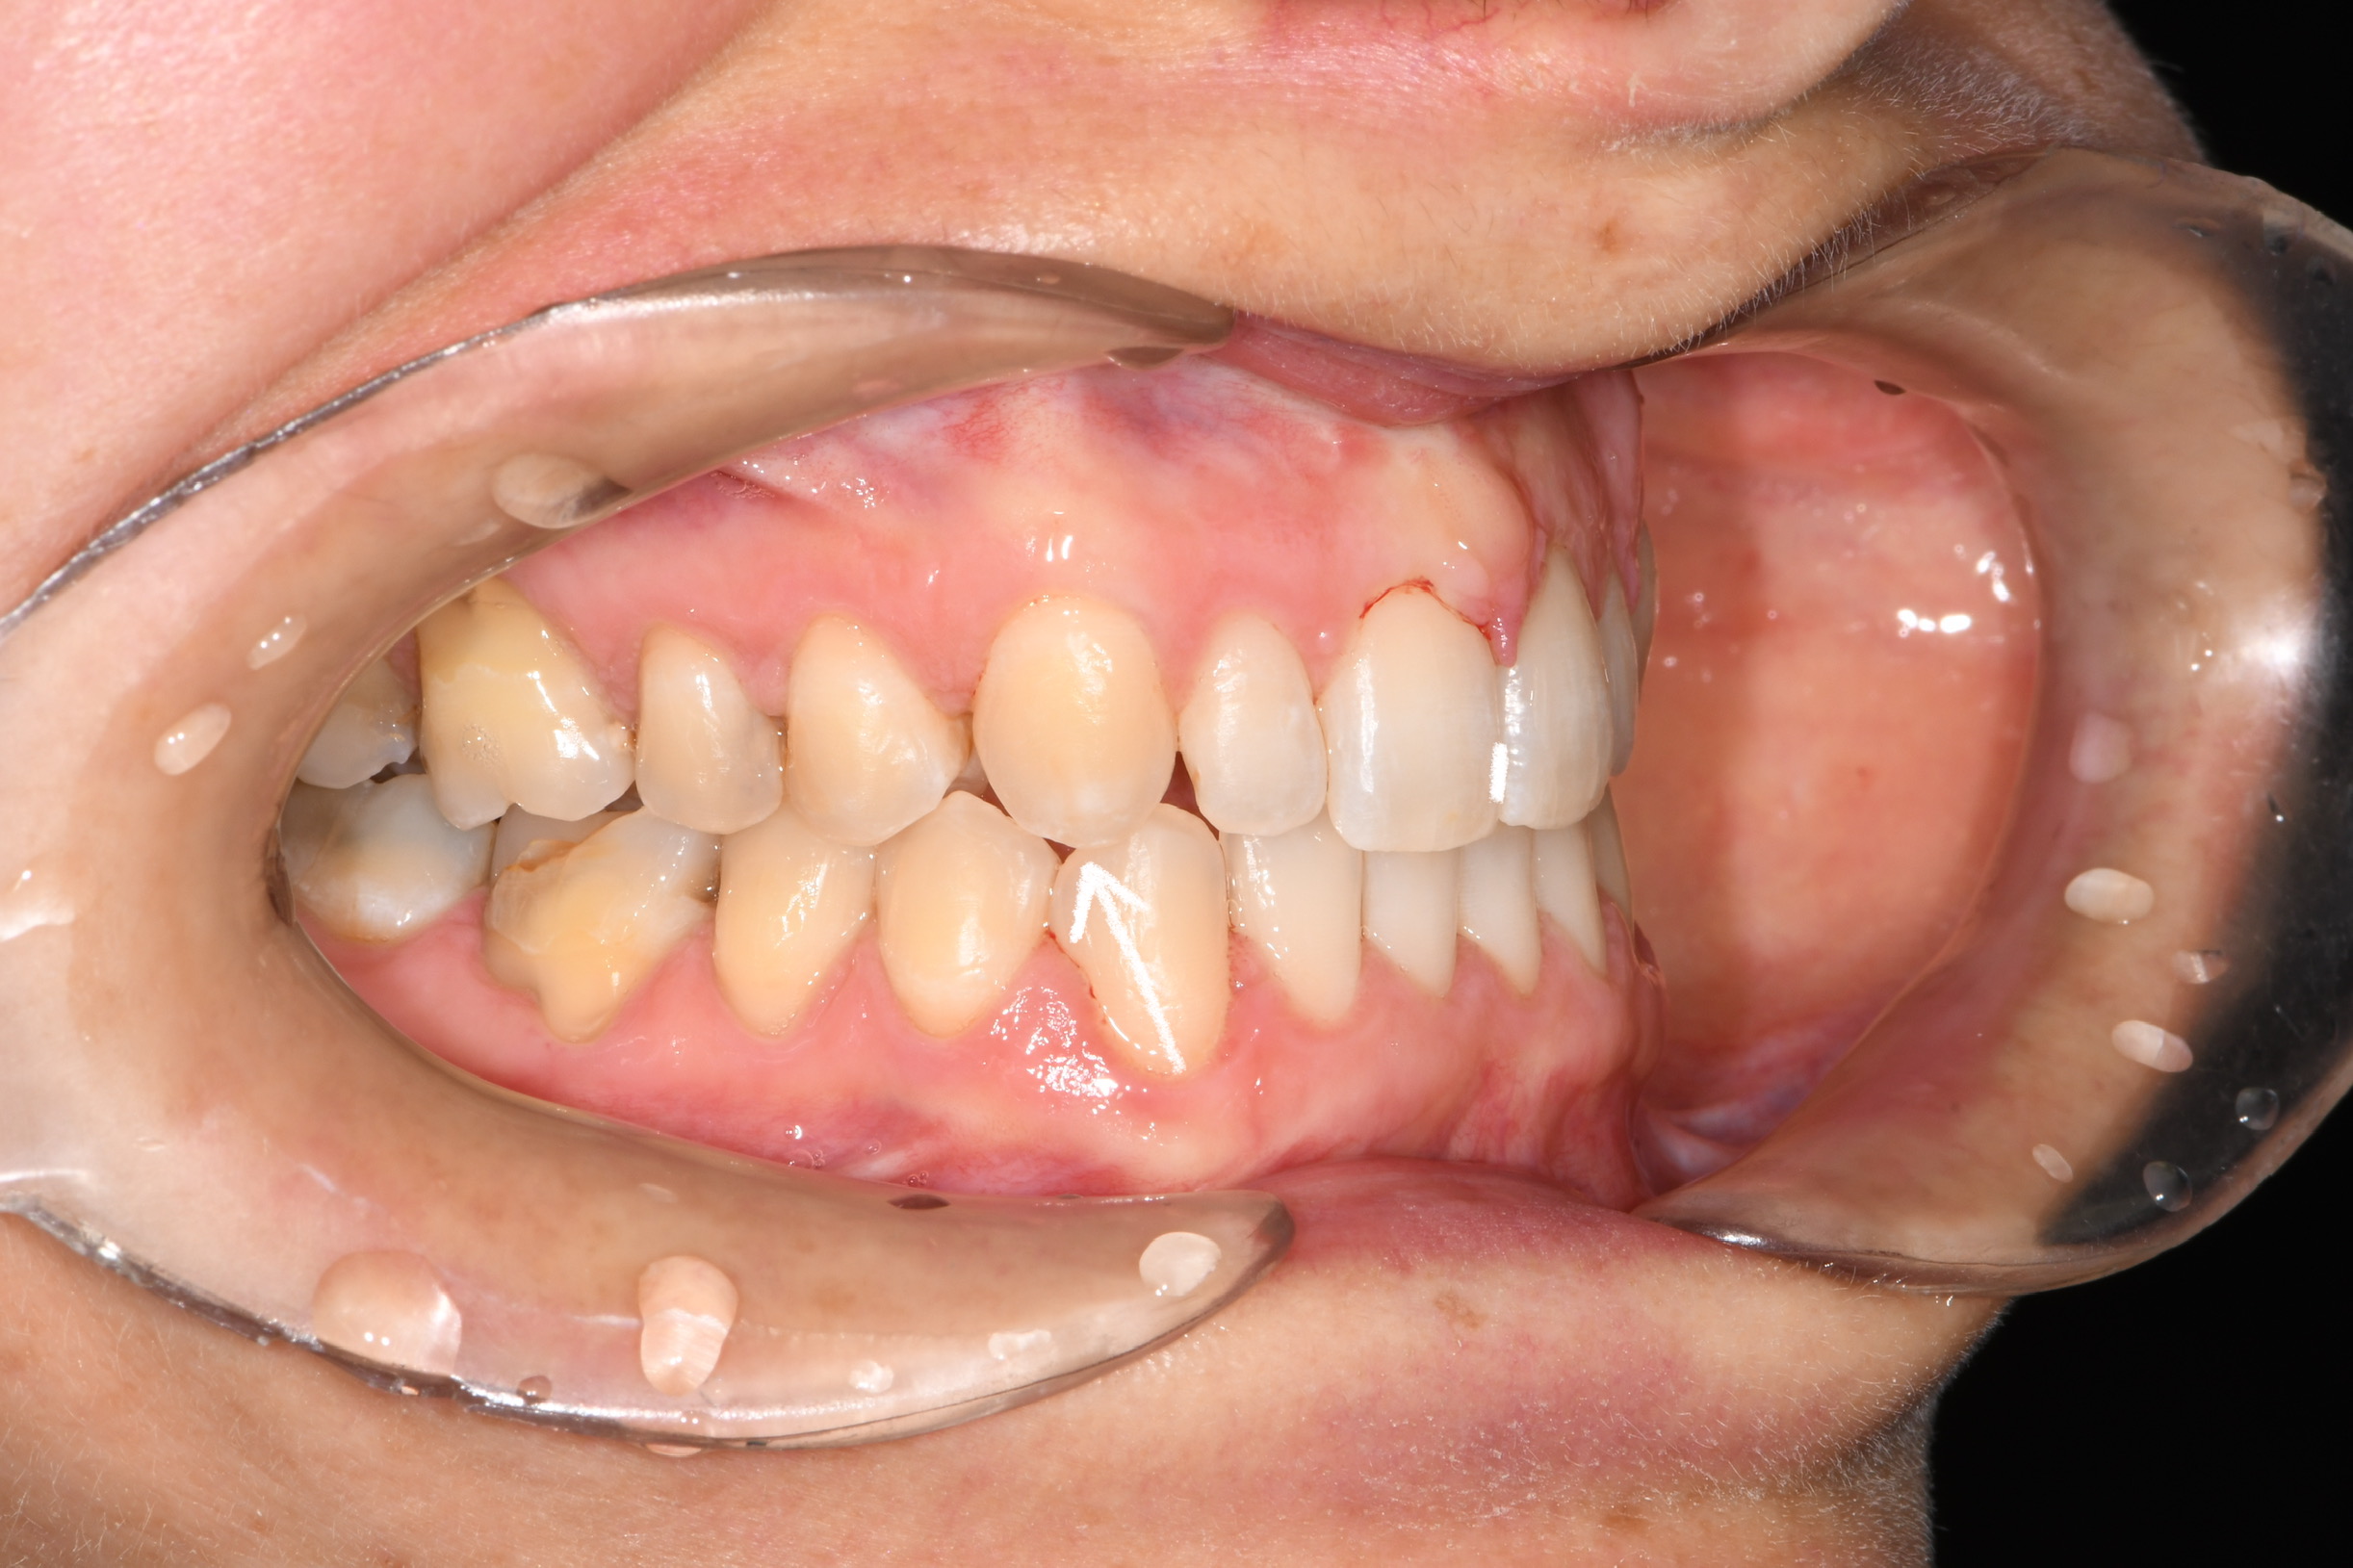

Az elmúlt évekből rengeteg szakmai referenciát tudnánk bemutatni, amelyek különböző fogszabályozási problémákat oldottak meg. Válogatva a több száz esetből, ezen az oldalon olyan képeket, információkat igyekeztünk bemutatni, amelyeknek a segítségével a jövőbeni pácienseinknek azt tudjuk üzenni: A Te fogsorod is lehet gyönyörű!

(Képeket a Pácienseink külön írásos beleegyezésével mutatjuk be!)